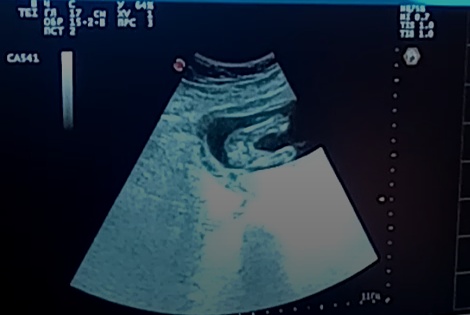

Юлия *

У меня есть скрин с видео в 16 нед. Ракурс с попы сзади. Между ножек пусто.

мой мальчишка, срок 17+4